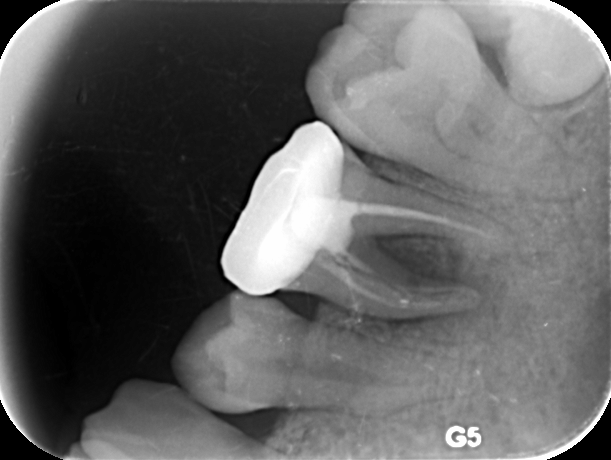

3、当根尖周炎由急性转化为慢性时,根尖周的牙槽骨将被破坏,X线片可以见到透射现象,由于牙槽骨本身经常处于吸收和重建的交替过程,在病变刺激减弱时,牙槽骨可发生重建,骨质增生,形成致密性骨炎,而出现X线阻射影像。>>点击在线咨询详情<<

牙博士引进的显微根管治疗成功率在90%以上,是目前保存患牙较好的治疗方法。显微根管治疗方法不仅可以保持天然牙齿排列的完整性,预防邻接牙齿的移位、蛀牙、牙周病的发生,还可以保存牙齿的完整,解决假牙制作上的种种困难,效果是非常好的。>>点击在线咨询详情<<